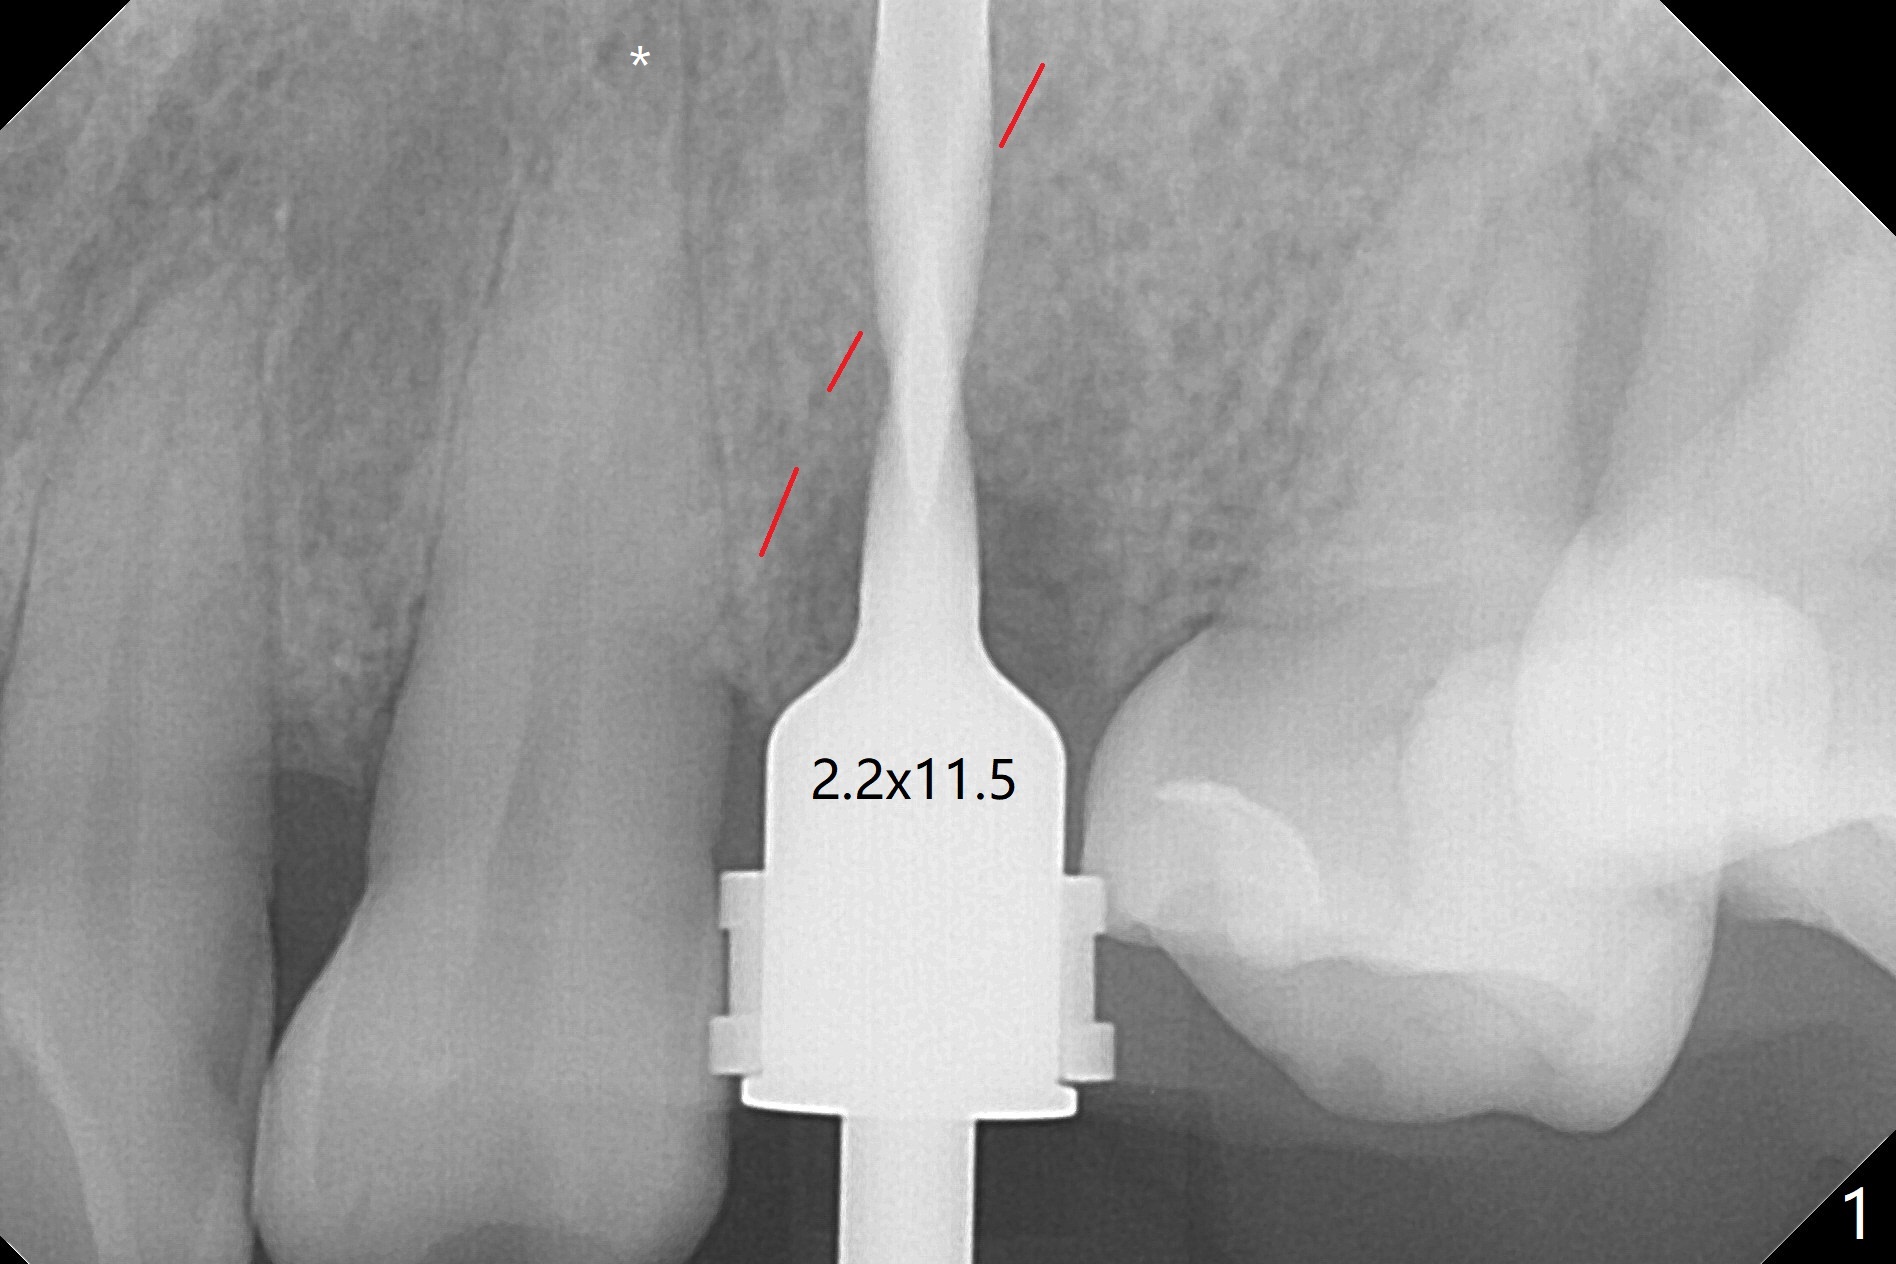

PA is taken after a 2.2 mm drill reaches the depth at #12, since osteotomy is initiated in the mesial slope of the socket (Fig.1 red dashed line) and the neighboring root (*) slightly curves distal. A 8.6x5 mm healing abutment is used to close the socket with the large mesiodistal space after bone graft (Fig.2 *). In contrast, the socket at #20 is large; a 4.5x4.5(3) mm cementation abutment is placed for an immediate provisional to keep autogenous bone (harvested from the site of #18) in place (Fig.3). Six months postop, the patient does not want implant FPD. She wants an additional implant at #19. Since the space between the implants #18 and 20 is 9.41 mm, a narrow implant is indicated (3 or 3.5 mm, Fig.4), in spite of the sufficient buccolingual width (Fig.5). The position and trajectory of the 1.2 mm initial drill and 3x10(2) mm 1-piece implant are acceptable with free hand (Fig.6,7). After 3-4 more turns, panoramic X-ray (Fig.8) and CT (Fig.9) are taken for 28-30 guide. It appears that the 1-piece implant is placed acceptable buccolingual (Fig.9 B). The implants at #12,18,20 (4.5 months postop with guide) are shown in Fig.10-12. It appears that guided surgery is superior in buccolingual position and trajectory to free hand. There is crestal remodeling without implant thread exposure 11 months postop (Fig.13).